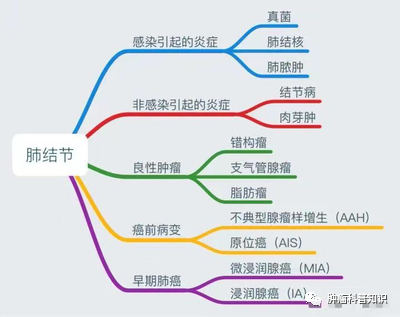

肺结节的定义及分类

肺结节是指肺内直径小于等于3cm的圆形或不规则形态病灶。根据肺结节的密度可分为三种,实性结节,部分实性结节(也叫混合性结节),磨玻璃结节。当检查到肺结节后,也不必紧张,绝大多数肺结节是良性,肺结节常见的是一些良性病变,很少会发展为癌,绝大部分会自然消失。 然而临床上确实有一些结节存在着癌变风险,这一过程是漫长的,一般需要5-10年甚至更长。从肺泡上皮增生-不典型增生-原位癌-微浸润性腺癌-浸润性腺癌逐步生长。我们今天来看看肺结节的癌变的过程。

肺结节的癌变的过程

癌前病变 - 腺瘤样不典型增生(AAH)

原位癌(AIS)

微浸润腺癌(MIA)

浸润腺癌(IAC)